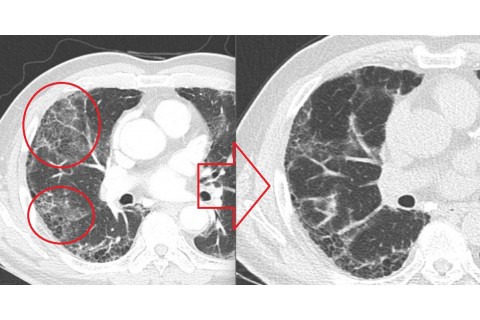

숨케어한의원에서는 전화예약을 받고 있습니다. 내원시 엑스레이, CT사진, 폐기능검사지를 가지고 오시면 자세한 상담이 가능합니다.